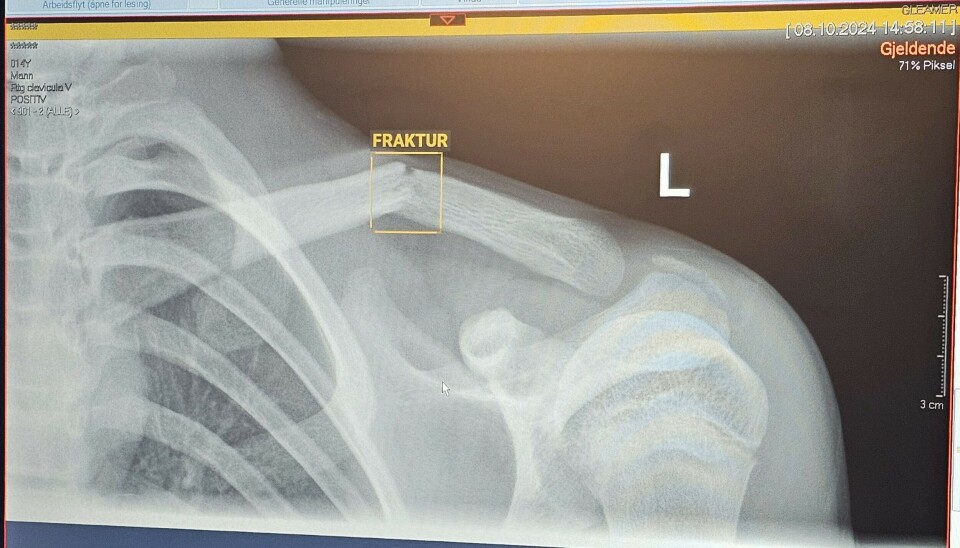

Og om litt skjer det. Linus Naas-Svorkmo (14) blir plutselig en hovedperson ved sykehuset. Han har falt og skadet seg på fotballbanen, og det er mistanke om claviculafraktur.

Bildene anonymiseres og sendes til en skyløsning hvor de analyseres ved hjelp av kunstig intelligens, og så sendes tilbake til dem. De blir ikke lagret noe sted utenfor Ahus, og ingen pasientopplysninger går ut av huset. Når de får svar, er bildene merket med "positivt", "usikkert" eller "negativt" med tanke på funn.